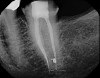

Accurate diagnosis is sometimes the most difficult aspect of daily clinical practice. CBCT has improved the trained practitioner's ability to find hidden periapical pathology, particularly in areas where structures such as the maxillary sinus and zygomatic arch, as well as thick cortical bone, can conceal periradicular lesions (Figure 7 and Figure 8).5-7

Fig 8. 3D CBCT image of tooth No. 3 revealing hidden periapical pathology.

Figure 8